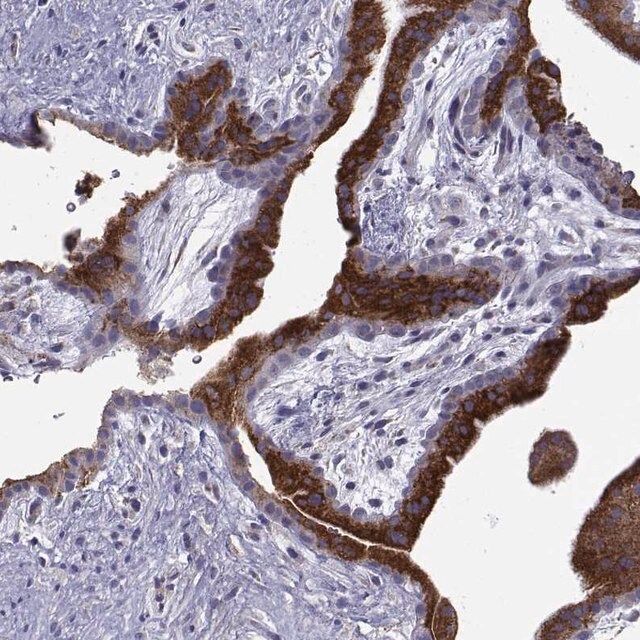

Anti-ERO1A antibody produced in rabbit

| Human Protein Atlas Number【人类蛋白质图谱编号】 | HPA026653 Human Protein Atlas characterization data |

| Immunogen【免疫原】 | endoplasmic reticulum oxidoreductase alpha |

| technique(s) | immunoblotting: 0.04-0.4 μg/mL immunohistochemistry: 1:1000-1:2500 |